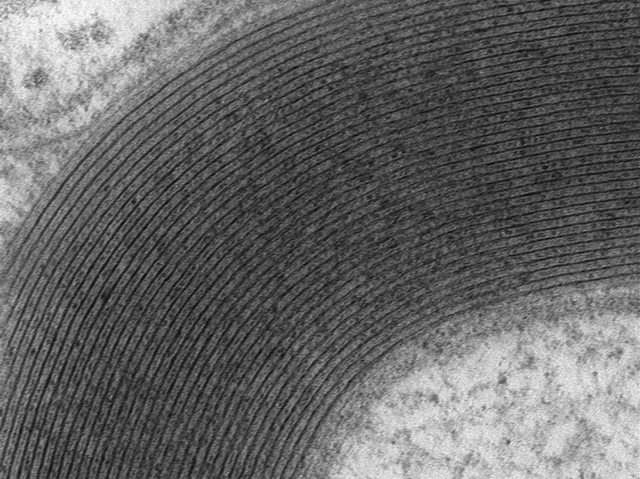

Sliced open with a diamond-edged knife, a nerve cell looks a bit like a tunnel. The sciatic nerve (lower right corner) carries electrical signals from the spinal cord down the leg – but not without some help. As the nerve develops, its body (known as an axon) is surrounded by Schwann cells – they treat axons a bit like sticks in a candy floss machine, wrapping them in layer upon layer of waxy myelin (black rings). Over 30 myelin rings can be counted around this nerve thanks to the detail of transmission electron microscopy. A myelin ‘sheath’ not only protects the sciatic nerve, but fine-tunes its electrical properties, shaping the sensations we feel in our lower limbs. Researchers have recently managed to grow stocks of fresh Schwann cells from stem cells found in human skin, an important step towards replacing myelin in patients with nerve injuries.